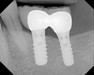

Type of Implants Endosteal (in the bone): This is the most commonly used type of implant. The various types include screws, cylinders or blades surgically placed into the jawbone. Each implant holds one or more prosthetic teeth. This type of implant is generally used as an alternative for patients with bridges or removable dentures.